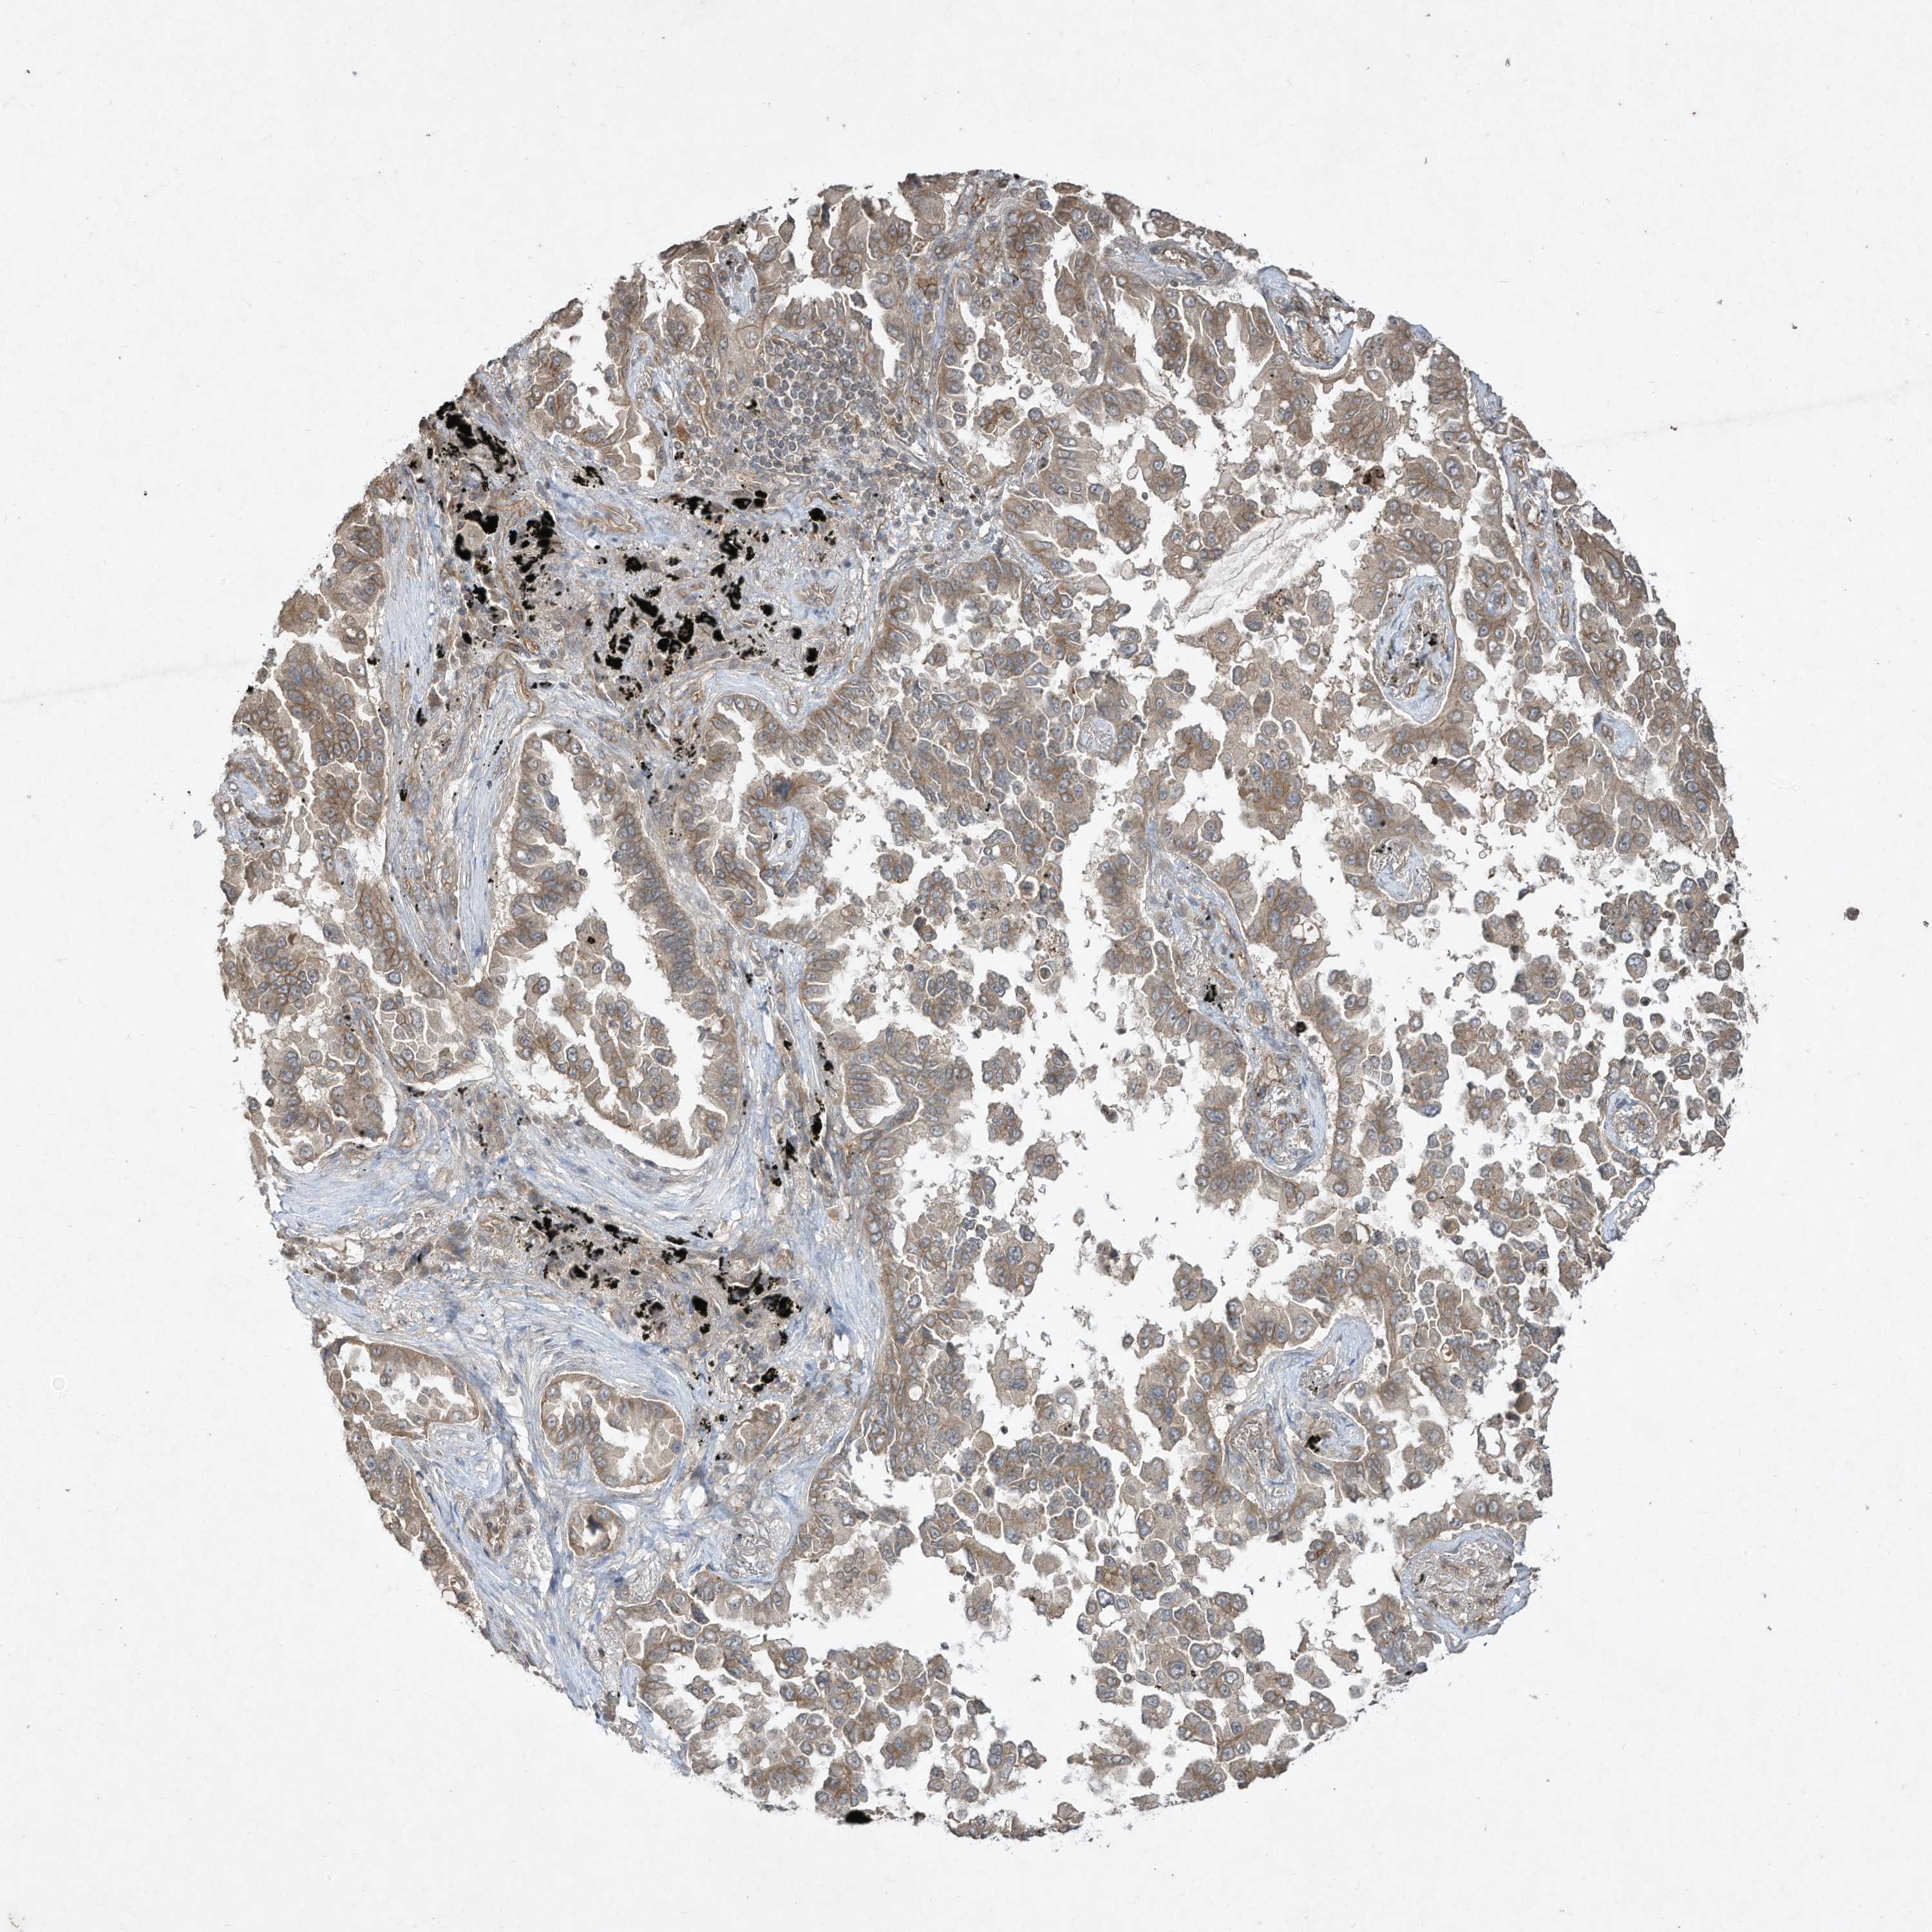

CANCER LUNG CANCER Show tissue menu

LUAD TCGA LUAD VALIDATION LUSC TCGA LUSC VALIDATION PROTEIN LUAD CPTAC PROTEIN LUSC CPTAC PROTEIN EXPRESSION

Average pTPM 11.4

Number of samples 497